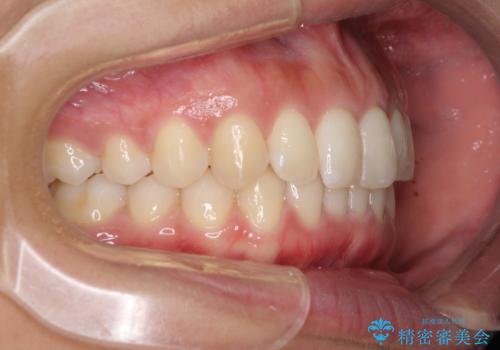

- 深い咬み合わせ(ディープバイト)と前歯のデコボコを気にして来院された患者様です。

インビザラインによる上下歯列の側方拡大と後方移動、IPR(歯と歯の間を削る)にるスペースの獲得により、デコボコとディープバイトを改善することとしました。

1日22時間の装着時間をしっかり守ってくださったので、予定通り1年で治療を終えることができました。

ディープバイトによる食いしばり癖も解消され、患者様には大変満足していただきました。